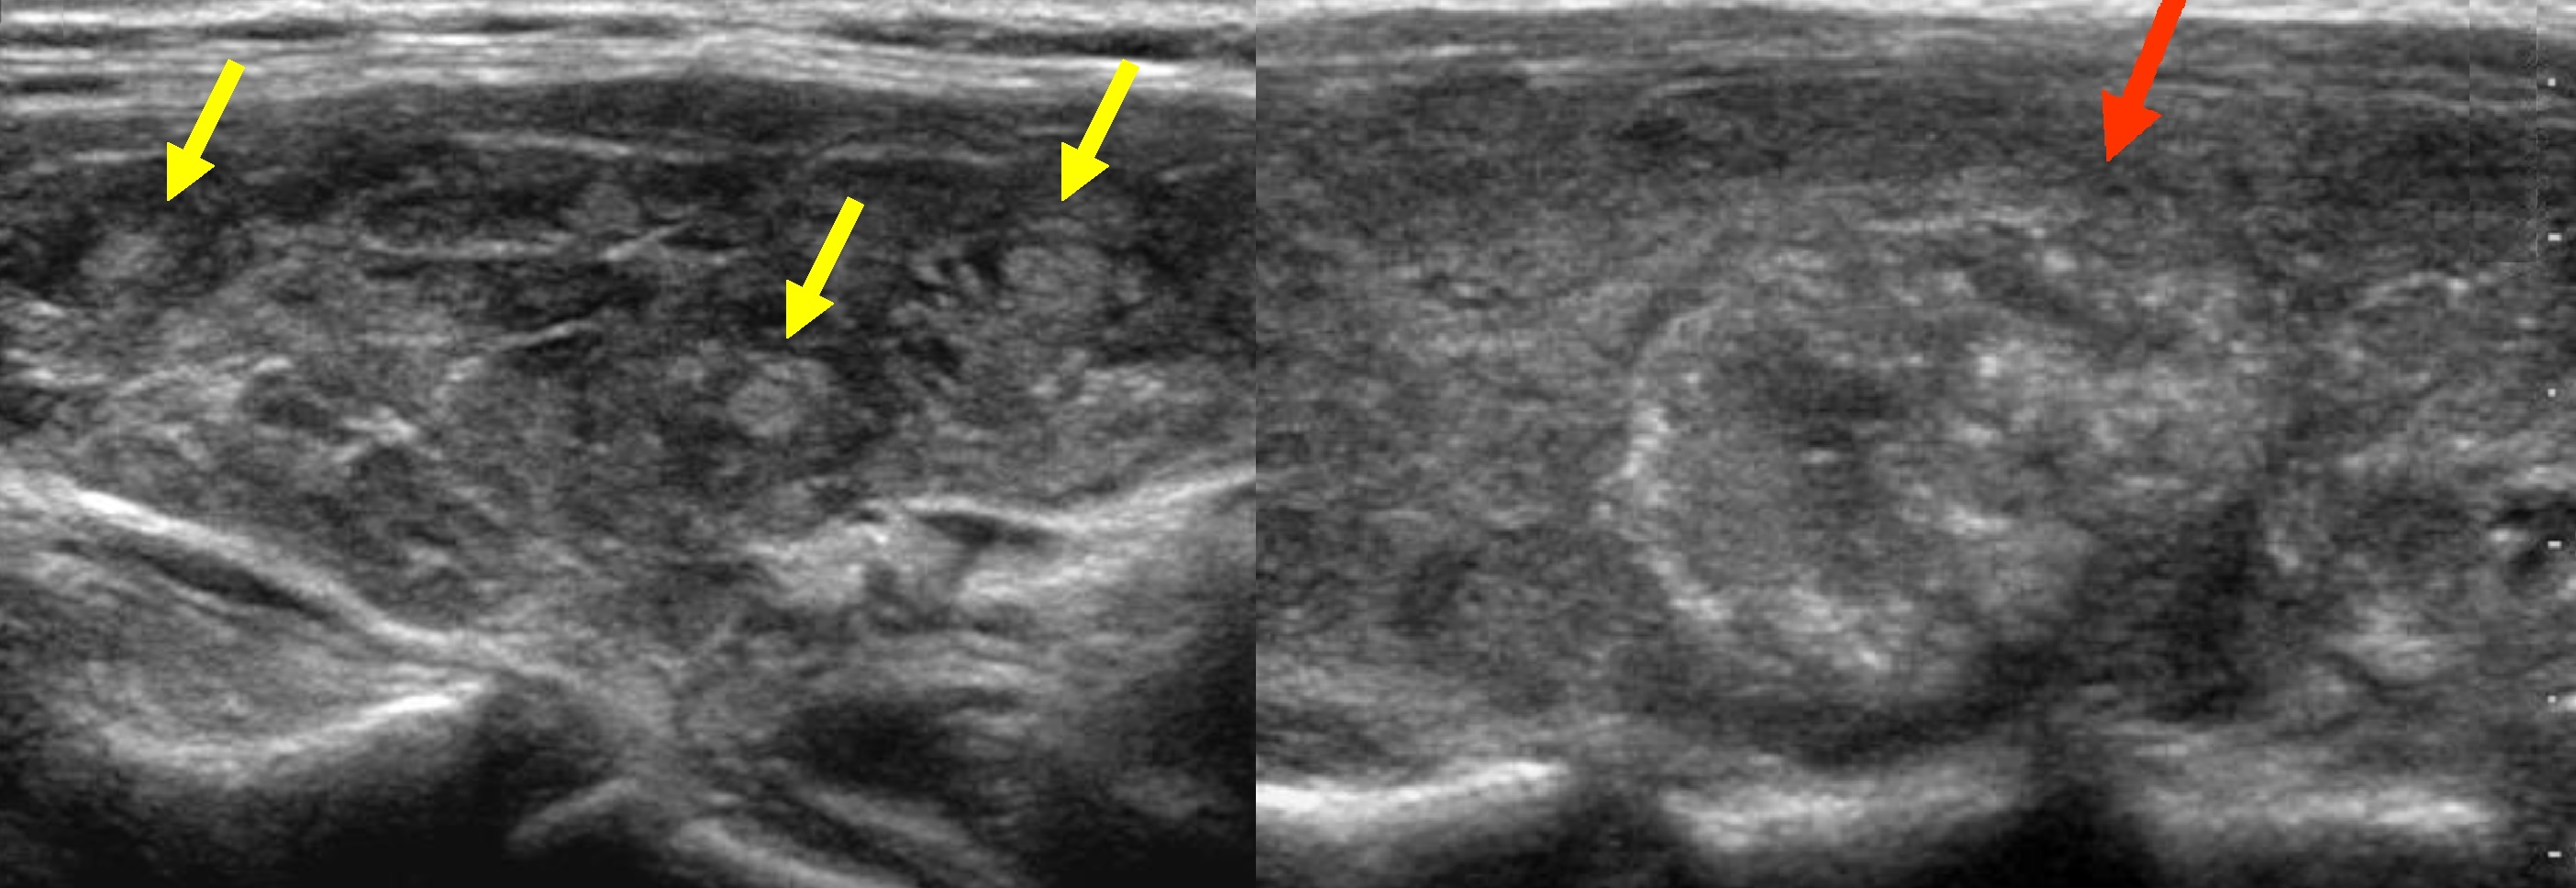

Различные ультразвуковые характеристики, такие как размер узелка, микрокальцификация, твердые элементы (по сравнению с кистозными), грубые кальцификации, текстура железы, кровоток внутри узелка, края узелка и форма (больше в высоту, чем в ширину) были оценены и записаны в все дела.В общей сложности 96 пациентов с диагнозом рака были сопоставлены по возрасту, полу и году ультразвукового исследования с 369 пациентами контрольной группы с доброкачественными узлами щитовидной железы.

В среднем на каждые 111 проведенных ультразвуковых исследований выявлялся 1 случай рака щитовидной железы. Узлы щитовидной железы были обнаружены у 97% пациентов с раком щитовидной железы и у 56% пациентов без рака щитовидной железы. Микрокальцификации были обнаружены в 38% злокачественных узлов и только в 5% доброкачественных, незлокачественных узелков. Риск рака увеличивается с размером узелка.Анализ данных этого исследования показал, что только 3 ультразвуковых признака были связаны с риском рака: микрокальцификация, размер узелков более 2 см и твердая форма.

Это исследование предполагает, что ультразвуковые характеристики микрокальцификатов, твердых узелков и размеров более 2 см могут быть использованы для выявления пациентов с высоким риском рака щитовидной железы. Напротив, другие исследования показали, что ультразвуковые признаки, такие как грубый кальцификат, более высокий, чем широкий, нерегулярные границы и повышенный кровоток внутри узелка, могут быть полезны для выявления рака щитовидной железы.В настоящее время рекомендации Американской тироидной ассоциации рекомендуют выполнять FNAB твердых узелков размером> 1 см и узелков> 0,5 см только в том случае, если у них есть подозрительные признаки, обнаруженные с помощью ультразвука.

Некоторые авторы предполагают, что гипоэхогенные твердые узелки размером более 1–1,5 см с макрокальцификациями следует проводить биопсию, а губчатые узелки и кисты не нуждаются в биопсии.